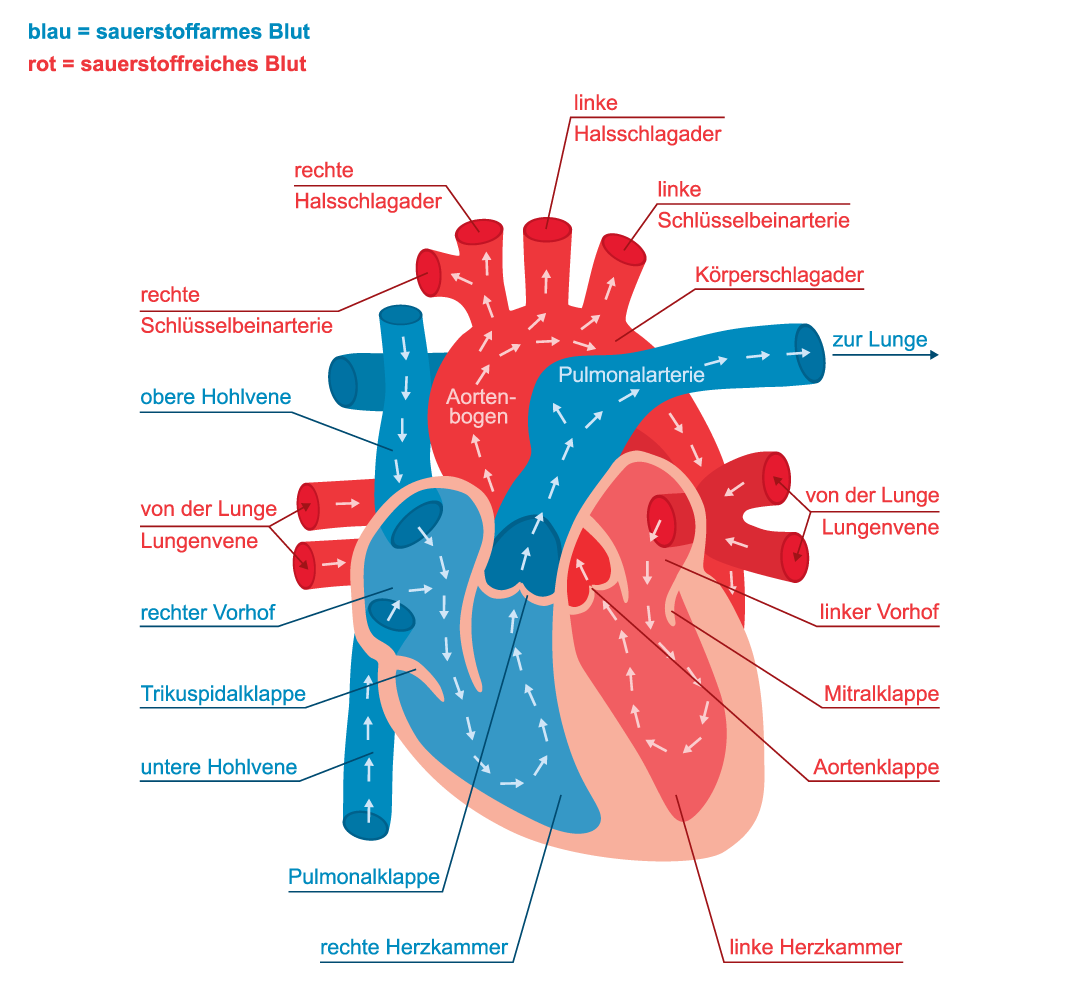

Die Pumpleistung ist die Menge des Blutes, die das Herz innerhalb einer bestimmten Zeit in den Blutkreislauf pumpt. Das gesunde Herz eines erwachsenen Menschen pumpt in Ruhe etwa 5 bis 6 Liter pro Minute. Bei einer körperlichen Belastung steigt dieses Herzminutenvolumen auf 20 bis 25 Liter. Krankheiten können die Pumpleistung des Herzens unnatürlich senken oder steigern.. In jeder Minute wird so einmal die gesamte Blutmenge – beim Erwachsenen fünf bis sechs Liter – durch den Körper befördert. Doch wie schafft das Herz jeden Tag diese Schwerstarbeit und wie funktioniert diese menschliche Pumpe? Herz-Kreislauf-System: So fließt das Blut. Das Herz ist das Zentrum des Blutkreislaufs.

Das Herzzeitvolumen (HZV, englisch cardiac output CO) ist das Volumen des Blutes, das pro Zeitspanne vom Herzen gepumpt wird (Volumenstrom).Die übliche Maßeinheit in der Humanmedizin ist Liter pro Minute, wobei dann vom Herzminutenvolumen (HMV), früher auch Minutenvolumen des Herzens, gesprochen wird.. Das Herzzeitvolumen ist ein Maß für die Pumpleistung des Herzens bezüglich der.. Der venöse Rückstrom zum Herzen bestimmt ganz wesentlich, wie viel Blut das Herz jede Minute auswirft. Abhängig von diesem Rückfluss pumpt das Herz automatisch das zurückströmende Blut in den Körperkreislauf. Je mehr Blut zurückströmt, desto mehr Blut wird vom Herzen ausgeworfen und umgekehrt.